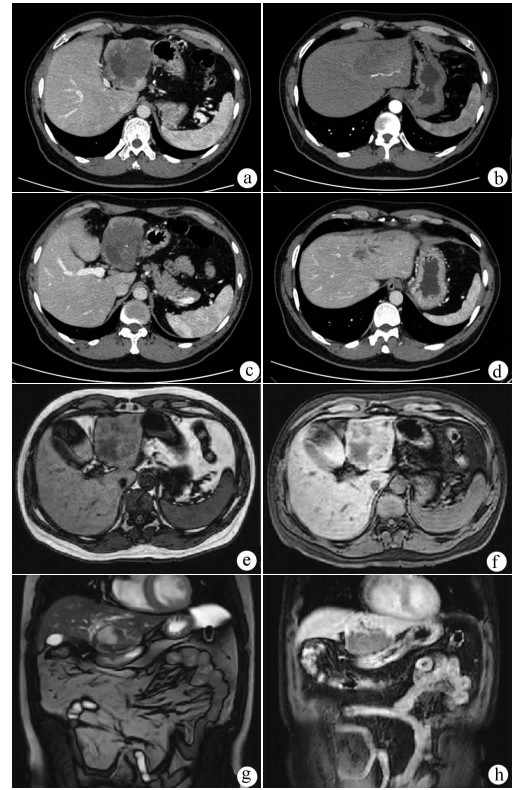

Hepatic alveolar echinococcosis misdiagnosed as intrahepatic cholangiocarcinoma: A case report

Kai ZHAO, Zhixin WANG, Shengbao WEN, Haijiu WANG, Haining FAN, Li REN

2021, 37(5): 1183-1185. DOI: 10.3969/j.issn.1001-5256.2021.05.042

Abstract(964) HTML (350) PDF (2157KB)(55)

Abstract: